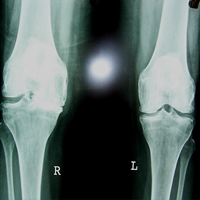

Case:1 TKR

Arthroscopy Surgeon in Ahmedabad

Pre-Op Lateral

Pre-Surgery